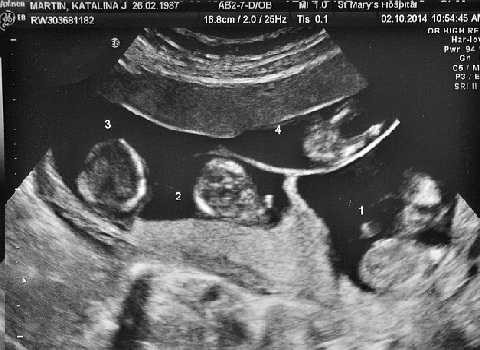

| Amelia, Sofia, Aston và Roman được thụ thai tự nhiên đã bốn tháng tuổi, mỗi bé lại được ra đời từ một trứng riêng biệt. |

Chỉ vài tháng sau đó, cô Martin phát hiện mình đang mang thai và đã đi siêu âm tại Bệnh viện Stepping Hill gần nhà, ở Stockport..

“Người siêu âm đã chụp chiếu khá lâu và cứ liên tục nhìn chăm chú vào màn hình” cô Martin kể lại.

Sau đó, cô Martin được thông báo là cô đang mang thai ba hoặc có thể là bốn em bé. “Tôi chỉ bật khóc. Tôi chưa bao giờ nghĩ tới điều kì diệu."